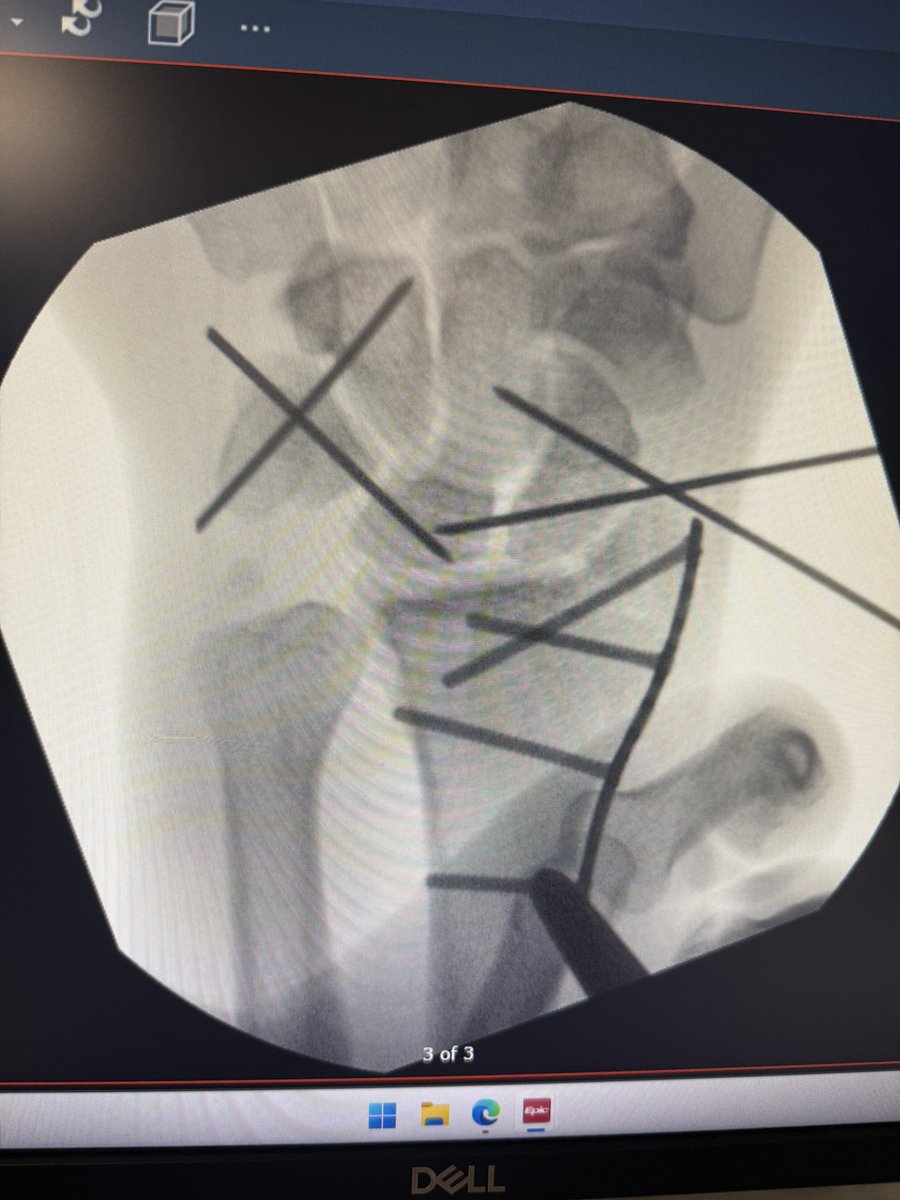

@RMexico11 So it was dislocated as well but they got all the bones and stuff back in place a little while ago and I will do surgery in the morning to add some pin screws plates